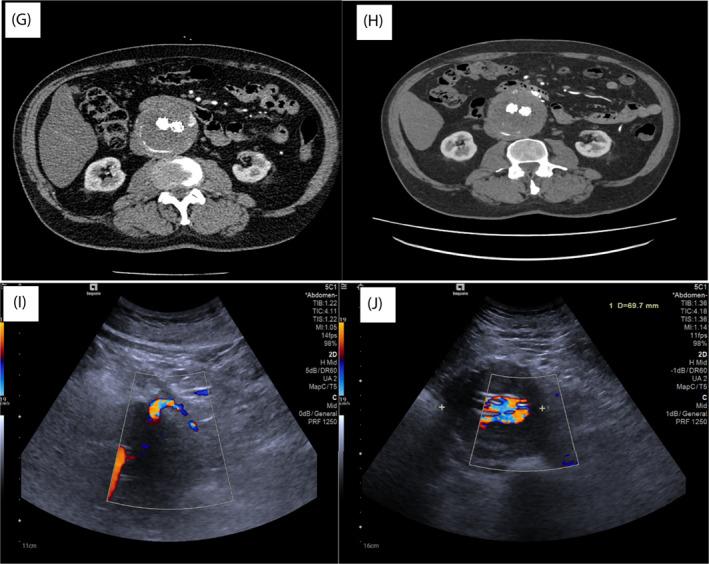

A 74-year old male underwent EVAR for a 5.8 cm infra-renal abdominal aortic aneurysm using an E-Tegra, Jotec Device (JOTEC Gmb, Lotzenäcker 23,D-72379 Hechingen). Surveillance contrast CT (CTA) over the ensuing 30 months confirmed progressive sac expansion.

RESULTS

ICG confirmed colonic perfusion via the marginals after IMA ligation. Total operative time 56 min < 50 mls blood loss and 1-day hospital stay. 3-month follow-up: CTA and ultrasound demonstrated complete resolution of T2E and adequately perfused colon.

我们描述了机器人修复血管内腹主动脉瘤修复(EVAR)后 II 型内漏(T2E)的技术操作细节。我们证明,吲哚菁绿(ICG)可在术中用于证明结扎供应动脉瘤囊的肠系膜下动脉(IMA)血管后结肠的灌注。

方法

一名 74 岁男性因 5.8cm 肾下型腹主动脉瘤接受 EVAR 治疗,使用 E-Tegra,Jotec 器械(JOTEC Gmb,Lotzenäcker 23,D-72379 Hechingen)。随后的 30 个月的监测对比 CT(CTA)证实了囊的进行性扩张。

结果

IMA 结扎后,ICG 通过边缘确认了结肠的灌注。总手术时间 56 分钟<50ml 失血量和 1 天住院时间。3 个月随访:CTA 和超声显示 T2E 完全缓解,结肠灌注充足。